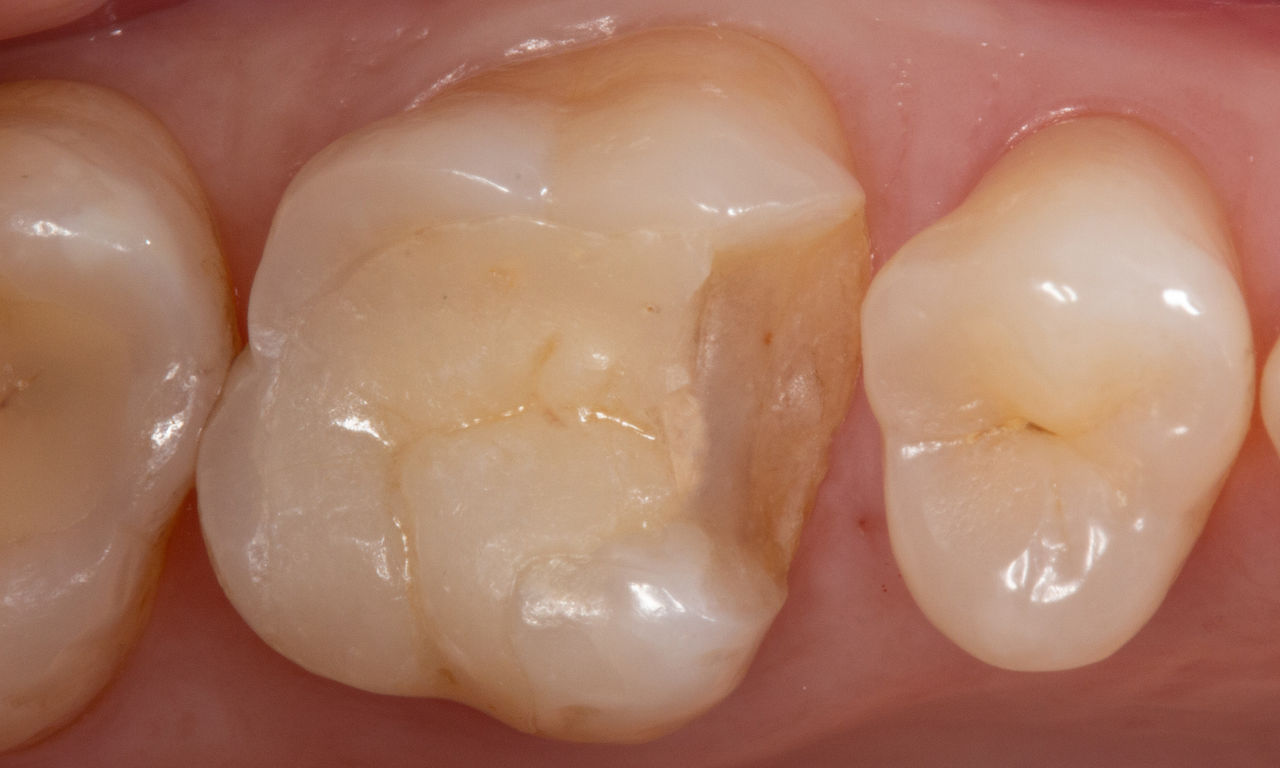

Avant : Restauration en céramique fracturée réalisée à partir d’une vitrocéramique renforcée à la leucite après une durée d’utilisation clinique de 12 ans.

Après : Restauration fabriquée en consultation à partir d’une céramique avancée au disilicate de lithium CEREC Tessera.